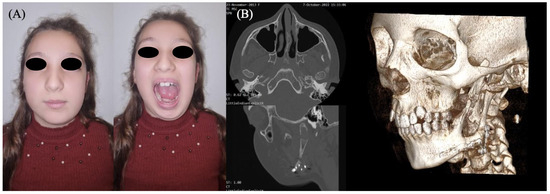

An 8-year-old female patient was referred to the Department of Oral and Maxillofacial Surgery of the Salus Italo-Albanian Hospital of Tirana for evaluation of a progressively enlarging, firm swelling involving the middle and lower thirds of the left hemiface (Figure 1). The lesion had been first noted approximately one year prior and had shown continuous enlargement over time. Intraoral examination revealed a mass involving the left mandibular alveolar ridge, with increased mobility of the posterior mandibular teeth upon palpation.

A panoramic radiograph demonstrated a multilocular radiolucent lesion with a “soap bubble” appearance, involving the entire left hemimandible up to the mental foramen, with extension to both the coronoid and condylar processes. Preoperative computed tomography (CT) confirmed the expansive lesion, extending from the mid-body of the mandible to the ascending ramus, including the coronoid and condylar apophyses (Figure 1).

Figure 1. (A) An 8-year-old patient with evident swelling of the middle and lower third of the left hemiface. (B) Panoramic radiograph and (C) CT scan revealing a large mass involving the body, angle, and ramus of the left mandible.